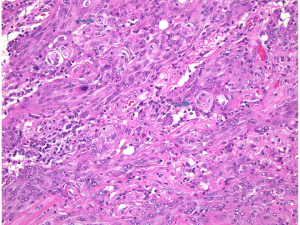

necrosis 壊死・atypical meningioma WHO grade 2 非定型髄膜腫

WHO grade 2 atypical meningioma (MIB-1 15%)に認められた壊死像です。この病理部分像からはgrade 2ですが,MIB-1も非常に高率です。さらに,多少なりとも核異型がみられるとgrade 3のanaplastic meningiomaになります。